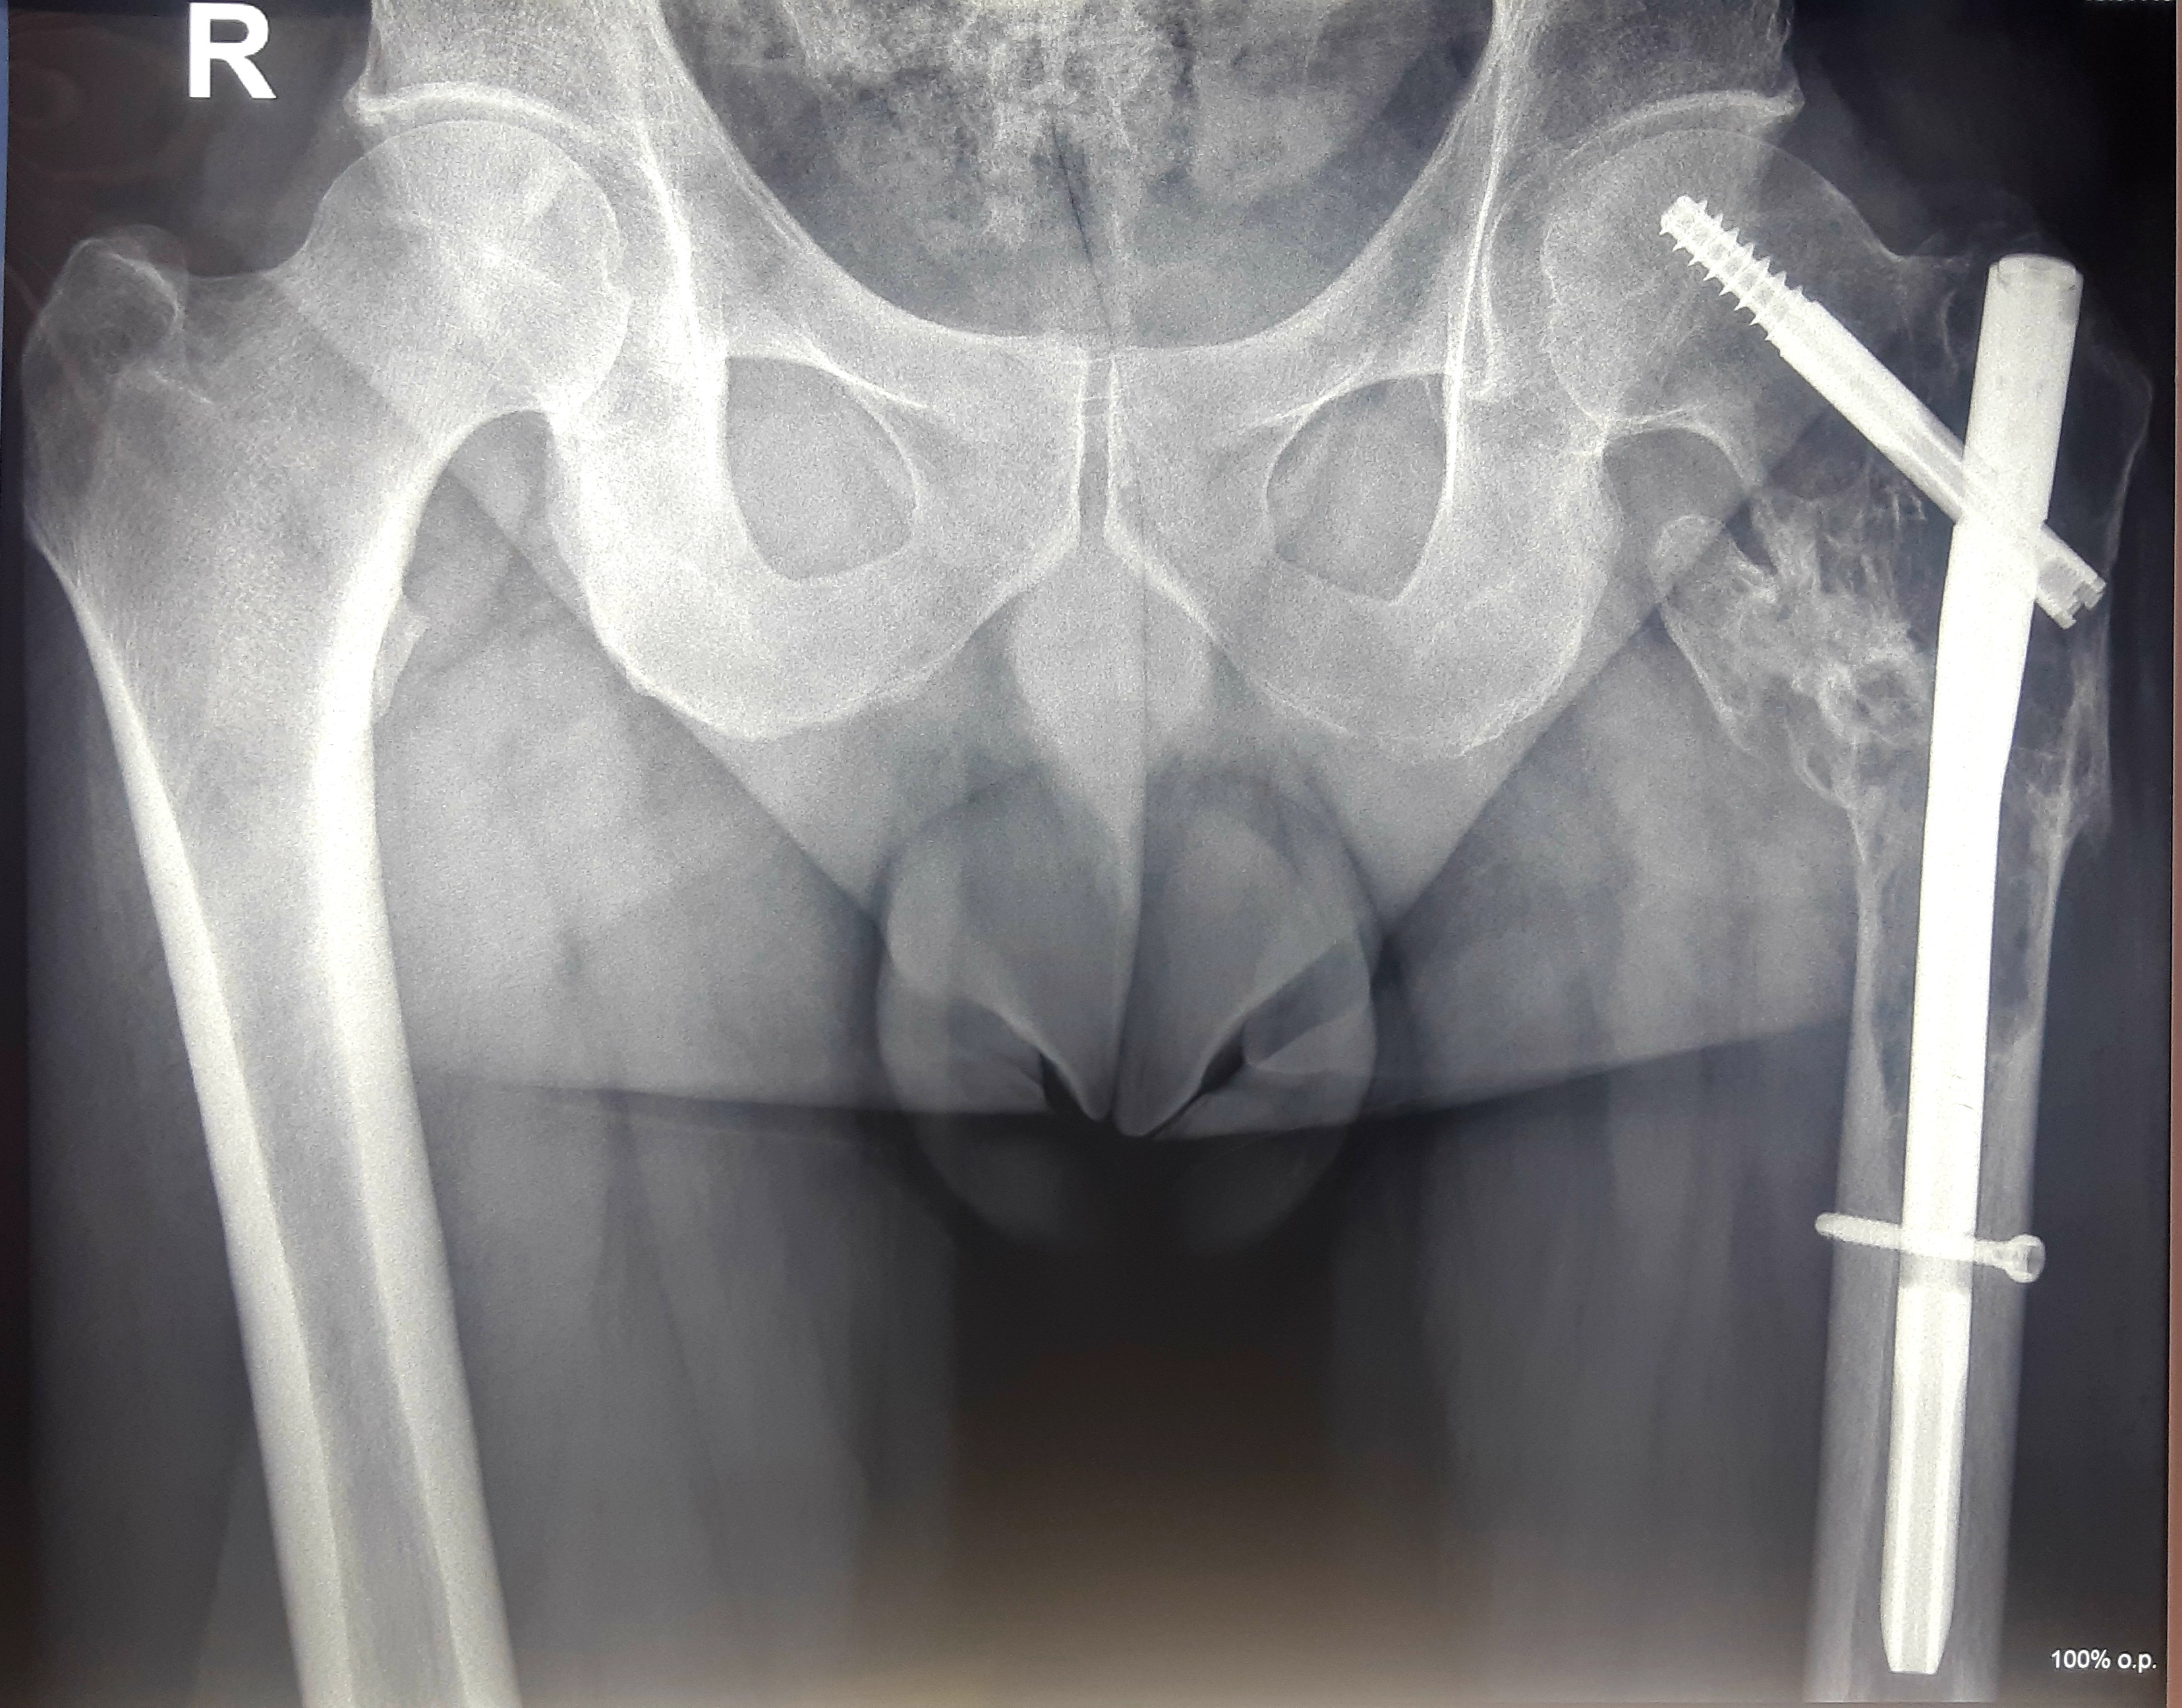

1 . ՌԴ-ում երկրորդային բնույթի կոտրվածքի ֆիքսացիա իրականացնելուց հետո՝ 40-ամյա բուժառուն դիմել է «Նաիրի» ԲԿ։ Բուժառուի մոտ ախտորոշվել է ոսկրային պլազմոցիտոմա։ Քիմոթերապիա ստանալուց հետո՝ 40-ամյա բուժառուն վիրահատվել է։ Կոնք-ազդրային հոդի հետ միասին հեռացվել է ազդրոսկրի վերին երրորդականը։

Առաջացած դեֆորմացիան շտկվել է էնդոպրոթեզով: «Նաիրի» ԲԿ-ի փորձառու թիմի և պրոֆեսիոնալ մոտեցման շնորհիվ՝ հաջողվել է պահպանել բուժառուի գործող վերջույթը։

Վիրահատությունից առաջ Վիրահատությունից հետո